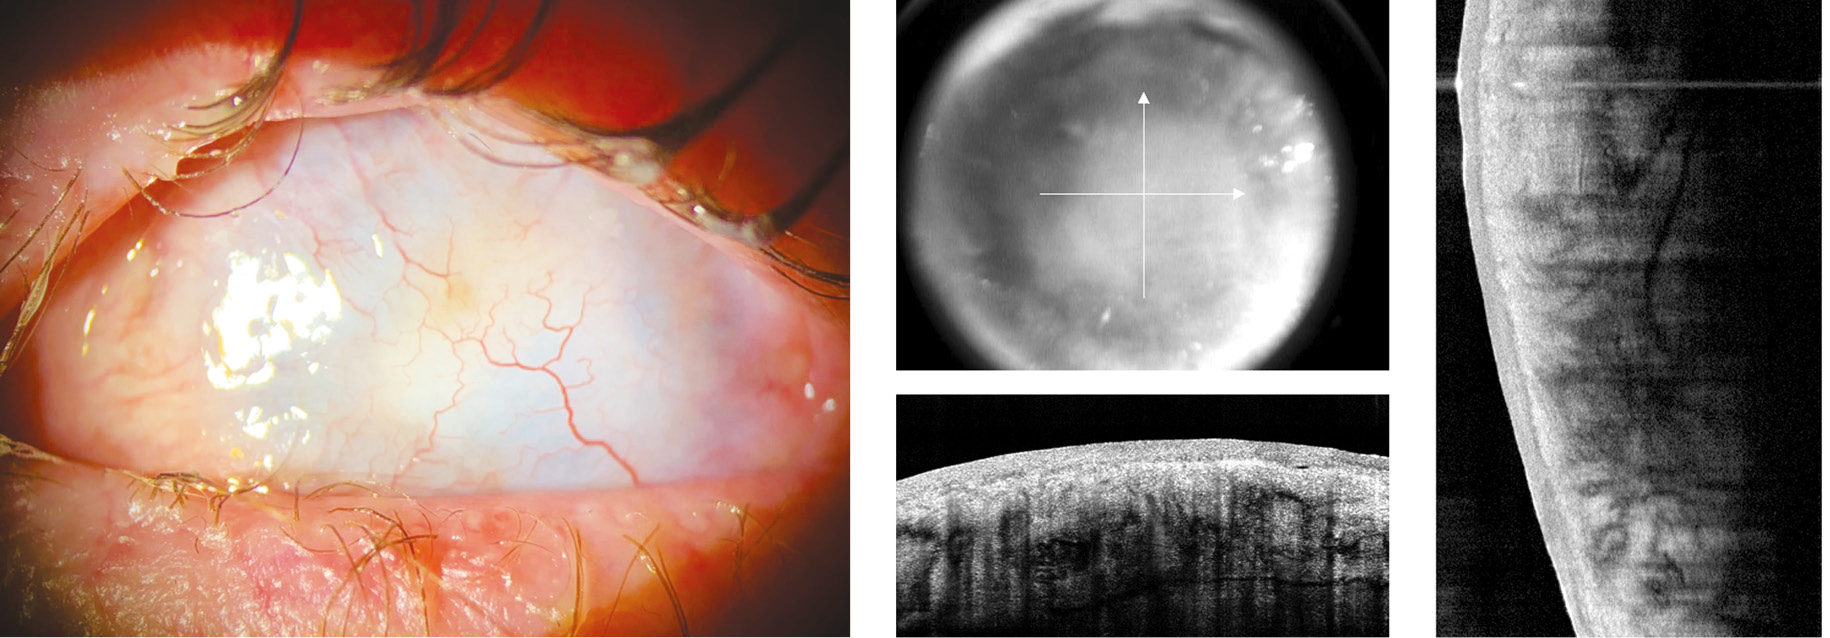

Fig. 2. The state of the left eye before the first keratoprosthetics stage: vascularized corneal leukoma with central thickness of about 1 mm

Рис. 2. Состояние левого глаза перед первым этапом кератопротезирования: сформировавшееся васкуляризированное бельмо роговицы 5-й категории с толщиной в центре около 1 мм

To restore visual function, it was decided to perform optical keratoprosthetics using the Fedorov–Zuev prosthesis [13] in the left eye. Sufficient thickness of the cornea in the center (about 1 mm) (Fig. 2) allowed performing the first stage of the keratoprosthetics (Fig. 3) in December 2022, i.e., implanting a full-thickness 8 mm supporting element into the vascularized corneal leukoma.

Fig. 3. The results of the first stage of Fyodorov–Zuev keratoprosthesis implantation into the left eye (positioning of the support kerato- prosthesis element into vascularized leucoma of the left eye cornea)

Рис. 3. Результаты первого этапа кератопротезирования (установка опорного элемента кератопротеза Фёдорова – Зуева в толщу васкуляризированного бельма роговицы левого глаза)

The postoperative period was uneventful, with no evidence of protrusion of the keratoprosthesis supporting element (outside or into the anterior chamber). Six months later, in May 2023, the second stage of the keratoprosthetics was performed: implantation of a 58 D optical cylinder with a protrusion height of 1.5 mm (Fig. 4).